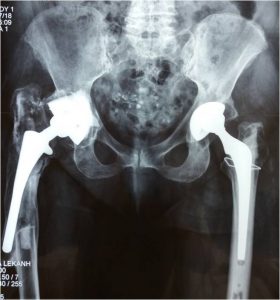

Στην ολική αρθροπλαστική ισχίου αντικαθιστούμε τις κατεστραμμένες αρθρικές επιφάνειες με μεταλλικές προθέσεις τιτανίου, που επιτρέπουν πλήρεις και ανώδυνες κινήσεις της άρθρωσης. Η εφαρμογή των πλέον σύγχρονων μεθόδων μικρής παρεμβατικότητας (MIS) και αποθεραπείας εγγυάται τα καλύτερα δυνατά αποτελέσματα με την άμεση μετεγχειρητική κινητοποίηση, την ολιγοήμερη παραμονή στην κλινική και την ταχύτερη επαναφορά του ασθενούς στις επιθυμητές καθημερινές του δραστηριότητες.

Σε αυτή την περίπτωση χρειάζεται αντικατάσταση της αρθροπλαστικής. Η αναθεώρηση (revision) αποτελεί ένα ιδαίτερο κεφάλαιο στην ορθοπαιδική χειρουργική και μια από τις πιο δύσκολες και απρόβλεπτες επεμβάσεις. Η εμπειρία του χειρουργού και το σωστά μελετημένο προεγχειρητικό πλάνο αποτελούν τον ακρογωνιαίο λίθο για την επιτυχία αυτής της κατηγορίας επεμβάσεων, καθώς η αναθεώρηση γίνεται όταν σε μια προηγουμένως διενεργηθείσα αρθροπλαστική έχουν δημιουργηθεί προβλήματα:

Η μεγάλη μας εμπειρία σε δύσκολες αναθεωρήσεις ισχίου και γόνατος από την πολυετή εργασία σε εξειδικευμένα κέντρα ολικών αρθροπλαστικών της Μεγάλης Βρετανίας και η εφαρμογή των πλέον σύγχρονων μεθόδων αποθεραπείας εγγυώνται τα καλύτερα δυνατά αποτελέσματα, με την άμεση μετεγχειρητική κινητοποίηση, την ολιγοήμερη παραμονή στην κλινική και την ταχύτατη επαναφορά του ασθενούς στις επιθυμητές καθημερινές του δραστηριότητες.